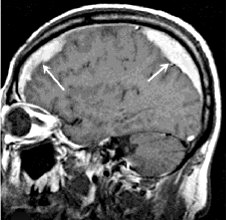

Медицинские аспекты и диагностика субдуральной гигромы мозга